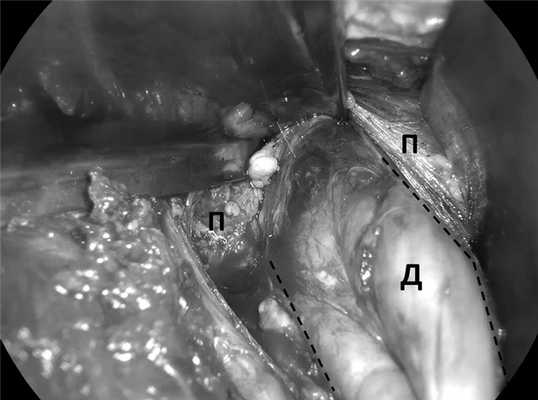

10.04.20 произведена операция. Положение пациента на спине с отведенной вверх и несколько вправо левой рукой. Под общим обезболиванием после предварительной разметки (рис. 2) выполнен доступ в левой подмышечной области длиной 5 см параллельно латеральному краю большой грудной мышцы. Отсепарован кожный лоскут вдоль грудной мышцы по направлению к нижней части шеи. После идентификации грудиноключично-сосцевидной мышцы доступ смещен по ее латеральному краю. Мышца отведена кверху при помощи средостенного ретрактора. Для контроля дальнейших манипуляций применяли эндоскопическую оптику (10 мм, 30°). Мобилизацию осуществляли при помощи ультразвуковых ножниц (Harmonic Ace + Shears, «Ethicon»). Идентифицированы лопаточно-подъязычная мышца, общая сонная артерия и яремная вена, которые отведены в сторону. Тупым и острым путем выделена левая доля щитовидной железы и отведена вверх. При этом отчетливо идентифицирован левый возвратный гортанный нерв. Дополнительно выделена и пересечена верхняя щитовидная артерия. Выявлен глоточно-пищеводный дивертикул, выделен из окружающих тканей на задней части глотки до шейки (рис. 3). Через подмышечный доступ ввели эндоскопический линейный сшивающий аппарат Echelon Flex 45 («Ethicon») с синей кассетой (рис. 4). Выполнено интраоперационное эндоскопическое исследование, осмотрено устье дивертикула и подтверждена правильность позиционирования аппарата для предотвращения сужения глотки и пищевода. Дивертикул прошит и отсечен. Дефект мышечной стенки ушит отдельными узловыми швами (Vicryl 3/0, «Ethicon») с помощью эндоскопических иглодержателей.

Рис. 3. Идентификация структур в зоне интереса (интраоперационная фотография).

Д — дивертикул; П — пищевод.